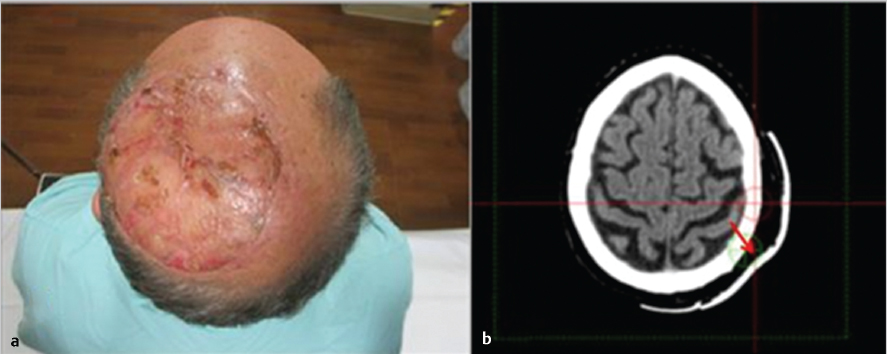

7 Role of Radiotherapy in the Treatment of Skin Malignancies Non-melanomatous skin cancers (NMSC), specifically basal cell carcinoma (BCC) and squamous cell carcinoma (SCC), are the most common malignancies in the United States. They are primarily managed surgically and carry an excellent prognosis, with a 1 to 5% rate of disease recurrence after complete excision and only exceedingly rare instances of distant metastasis. Historically, radiotherapy played a prominent role in the definitive management of these cancers as an alternative to surgical resection, especially in cosmetically sensitive areas. With the improvement in surgical techniques in recent decades, especially the widespread use of Mohs micrographic surgery (MMS), the use of curative radiation for skin cancers has declined. However, radiation is still commonly used in the definitive setting for patients with NMSC who are poor surgical candidates or have larger lesions in cosmetically sensitive regions of the face, and in the postoperative setting for more advanced tumors that have high-risk pathologic features that are associated with excessive risks of locoregional recurrence after surgery alone. Radiotherapy plays a similar role in the postoperative management of cutaneous melanoma. Radiation also offers excellent palliation for noncurable patients. This chapter reviews common indications, dose and fractionation schedules, techniques, and oncologic and cosmetic outcomes for radiotherapy for NMSC and melanoma ( Both surgery and RT can offer excellent cure rates for the management of early-stage NMSC. Surgery is typically the preferred method of treatment, given it can be performed in a single session, and has been associated with superior oncologic and cosmetic outcomes. One prospective randomized study compared the outcomes of MMS and definitive RT in 347 patients with less than 4 cm BCC of the face. The local failure rate was 0.7% for patients treated with MMS and 7.5% for patients treated with RT. Additionally, the cosmetic outcome was rated “good” or better more often in those patients who underwent surgery (87 vs. 69%).1 Though the technique of RT was not controlled (55% received interstitial brachytherapy and 45% received orthovoltage therapy), which could have affected the quality of the comparison, as the only randomized study, this trial remains pivotal in guiding medical decision making. A variety of factors can influence the decision to favor RT rather than surgery for NMSC. Typical contraindications to definitive RT include very large tumors and those with bone and/or cartilage invasion, given that control rates are typically inferior, as well as recurrent tumors that have been previously radiated or arise in an area of previous radiotherapy. Radiation should also be avoided in patients with genetic radiosensitivity syndromes, such as xeroderma pigmentosum and basal cell nevus syndrome, and in those with active connective tissue diseases, such as scleroderma and systemic lupus erythematosus.2 Patients who are candidates for definitive RT include those with unresectable disease, older patients with comorbidities limiting their surgical options, and patients with lesions involving the eyelid, canthi of the eye (especially those who carry surgical risk to the lacrimal duct), external ear ( Fig. 7.1 A modern linear accelerator, capable of delivering photon and electron radiotherapy with image guidance provided by cone beam CT (red arrow). A robust literature, much of it older when RT was more commonly used, supports the safety and efficacy of definitive RT for many of these aforementioned types of patients. A review of 986 BCC and SCC of the skin overlying the eyelid treated with definitive RT demonstrated a 5-year cure rate of 96.4%.3 A review of 334 BCC and SCC of the external ear at the Princess Margaret Hospital treated with definitive RT demonstrated a 2-year local control rate of 87%, with severe late toxicity noted in only 7% of patients.4 A review of 100 patients with SCC of the nasal skin at the Princess Margaret Hospital treated with definitive RT demonstrated a 2-year local control rate of 90%, with no severe toxicities observed.5 Fig. 7.2 (a) SCC of the helix of the left ear with bleeding (baseline). (b) After treatment with definitive radiation therapy (50 Gy in 20 fractions with electrons). There was complete remission with excellent cosmesis. Fig. 7.3 (a) A 96-year-old patient with right retroauricular BCC, T2N0M0 (baseline). (b) One month after treatment with definitive radiation therapy (50 Gy in 20 fractions with electrons). While definitive RT monotherapy can provide effective tumor control for T1–3N0 NMSC, T4 tumors and those with nodal metastases demonstrate inferior outcomes. Initial surgical management is recommended in these patients, often followed by adjuvant radiotherapy. T4 disease is defined as tumor invasion into the axial or appendicular skeleton or perineural invasion (PNI) of the skull base. The University of Florida reported a local control rate of just 53% at 5 years in patients with T4 BCC and SCC.6,7 In a review of 68 T4 BCC and SCC of the skin of the head and neck treated with definitive RT, local control rates were lower in patients with recurrent disease, compared to primary lesions (41 vs. 67%; p = 0.07) and the three most important prognostic indicators for inferior local control and cause-specific survival rates were bone involvement (p < 0.01), recurrent lesions (p < 0.01), and nerve involvement (p < 0.02).6 Even the more favorable lesions had local control rates of less than 70%. Similarly, a large retrospective review which included 531 BCC and SCC treated with definitive RT demonstrated local control rates of 94 and 89% for primary BCC and SCC tumors, respectively, and 86 and 68% for BCC and SCC recurrent tumors, respectively.8 In patients with nodal metastases, locoregional recurrence rates with definitive RT alone range from 30 to 50% and cancer-related mortality is as high as 30%.9 Such suboptimal outcomes support the use of intensification of treatment and multimodal therapy for these patients with advanced disease. In patients who are not eligible for initial surgical resection, concurrent cisplatin-based chemotherapy can be considered to enhance the effectiveness of radiotherapy. While there is no high-quality evidence demonstrating clear benefit to such an approach in cutaneous malignancies, many head and neck oncologists extrapolate from the mucosal SCC of the head and neck, where concurrent chemotherapy significantly improves disease control and survival in the setting of locally advanced disease treated nonoperatively.10 Fig. 7.5 A patient with multifocal BCC 3 months after treatment with definitive radiation therapy (40 Gy in 10 fractions with electrons). Postoperative RT is rarely used for BCC. Patients with BCC have an exceedingly low risk of recurrence after surgery alone, and even patients with a positive margin, focal cartilage invasion, or PNI are often still candidates for close observation and salvage re-resection if needed.11,12 However, postoperative RT is often considered in cases where there are persistently positive margins after multiple resections, T4 disease that extensively invades bone or soft tissue, lymph node metastasis, or clinically apparent PNI ( Postoperative RT is much more commonly used in resected SCC ( Retrospective data have demonstrated high rates of local recurrence in patients with T4 tumors managed with surgery alone.7 In addition, the rate of occult lymph node metastasis is high, ranging from 29 to 50%, in patients with advanced T-stage disease. In patients with deeply infiltrative (≥ 8 mm) tumors, or tumors that extensively invade deep subcutaneous fat, occult lymph node metastasis can be as high as 30%.9 Patients with recurrent primary tumors, PNI, lymphovascular space invasion, and those that are immunosuppressed are at significantly higher risk for having lymph node metastases and should undergo careful evaluation for regional disease with a contrast-enhanced diagnostic neck computed tomography (CT) and/or a positron emission tomography scan.14,15,16 In these patients, sentinel lymph node biopsy and/or neck dissection is recommended in conjunction with resection of the primary tumor. Postoperative RT can also be useful as an elective treatment to the undissected neck. Fig. 7.6 (a) A patient with right brow/forehead SCC (baseline). (b) One month after definitive radiation therapy (45 Gy in 15 fractions with electrons). Fig. 7.7 (a) An 88-year-old man with left temporal SCC in situ (baseline). (b) One month after treatment with definitive radiation therapy (30 Gy in five fractions with electrons). For patients with clinically involved lymph nodes, a therapeutic neck dissection followed by postoperative RT is the current standard of care. Although lymph node metastases are rare in SCC of the skin overall (~ 5%), they are clearly associated with a poor prognosis. After neck dissection alone, locoregional recurrence rates are 11 to 38% and even after multimodality therapy, the 5-year disease-free survival rates are 60 to 70%. Independent predictors of worse survival in this population include increased nodal size ≥ 3 cm, multiple lymph node involvement, extracapsular extension, incompletely excised nodes, and surgery monotherapy.15,16,17 A review of 167 patients in Australia with SCC metastatic to the parotid or cervical nodes compared outcomes for surgery versus combination of surgery and postoperative RT at a median dose of 60 Gy in 30 fractions. The use of postoperative RT was associated with significantly lower rates of locoregional recurrence (20 vs. 43%), and higher 5-year disease free (73 vs. 54%; p = 0.004), and 5-year overall survival (66 vs. 27%; p = 0.003) compared to patients who received surgery alone.16 Similar results supporting the benefit of postoperative RT for locoregional control and 5-year disease-free survival in patients with cutaneous SCC metastatic to lymph nodes and/or periparotid lymph nodes have been reproduced in a number of retrospective reviews.18,19,20,21 For patients who received lymph node dissection for primary SCC located on the trunk or extremities, postoperative RT is typically recommended when multiple nodes are involved or extracapsular extension is present. Similar to mucosal SCC of the head and neck, RT can be avoided in immunocompetent patients with a single involved lymph node, smaller than 3 cm, without extracapsular extension on parotidectomy or cervical lymph node dissection, as rate of regional recurrence is less than 5%.22 Fig. 7.9 A 91-year-old man with a history of extreme kyphosis and multiple facial SCC, who presented with a rapidly enlarging right neck mass, treated with surgical resection and free flap reconstruction. (a) Axial slice depicting isodose coverage of the neck bed with electron radiation therapy. (b) Extreme kyphosis dose coverage using 30 Gy in five fractions twice weekly. Fig. 7.10 A 63-year-old man with multiple recurrent SCC of the right temple with Mohs map overlying the site of the tumor. Fig. 7.11 (a) Coronal CT slice of dose distribution for postoperative radiation therapy after Mohs surgery for tumor depicted in PNI, while not common (5–10% of SCC), is another important risk factor for recurrence that should be weighed in the decision to administer adjuvant RT. PNI is typically divided into clinical and microscopic PNI. Clinical PNI is defined by neurologic manifestations, most commonly involving the trigeminal or facial nerves, leading to pain, paresthesias, paralysis, formication (the sensation of bugs crawling on the skin), or radiographic evidence of nerve enhancement.23,24 Microscopic PNI is appreciated only histologically and is identified after surgery in a patient who was asymptomatic preoperatively. PNI is important given it is associated with increased risks of local recurrence as well as regional and distant metastases. Factors associated with increased risk for SCC with PNI include male sex, tumor size greater than 2 cm, midfacial tumor location, recurrent tumor, and poorly differentiated subtypes.25 The degree of PNI is predictive of risk of recurrence; therefore, a careful history as well as physical and imaging examination is critical. Magnetic resonance imaging (MRI) has the advantage of identifying the extent of macroscopic disease through nerve enlargement or enhancement or obliteration of the normal fat plane surrounding a nerve ( The difference between clinical and microscopic PNI was highlighted in a series from the University of Florida which compared the outcomes of patients with PNI treated aggressively with surgery and postoperative RT. Those with clinical PNI had significantly lower 5-year rates of local control (57 vs. 90%; p = < 0.001) and overall survival (57 vs. 69%; p = 0.03) compared to those found to have microscopic PNI.13,23 RT is therefore always recommended in cases of clinical PNI. The role of postoperative RT in patients with pathologic PNI is less clear. Lin et al found that focal versus extensive microscopic PNI carries different prognoses, with relapse-free survival better in the former group (86 vs. 74%; p =0.1).24 Unfortunately, the distinction between focal and extensive was not well defined. As such, adjuvant RT is not recommended in immunocompetent patients with nonrecurrent disease, in whom one or two isolated areas of PNI are found in small unnamed nerves, with a diameter of less than 0.1 mm, given the outcome is expected to be fairly good with surgery alone. However, patients with microscopic PNI, that is multifocal, involves larger nerves (> 0.1 mm in diameter) and named nerves, or occurs in immunosuppressed patients, are at higher risk and thus adjuvant RT is recommended.2,25 For irradiation of clinical PNI, the clinical target volume should include areas at high risk of failure, specifically the involved nerve, the portion of the nerve proximally at the skull base, the distal skin innervated by the nerve, major communicating branches, and the compartment in which the nerve is embedded.26 For example, for patients with CN VII involvement, the area of treatment should be tracked back to the nerve’s exit through the stylomastoid foramen, with care taken to administer adequate coverage of the geniculate ganglion by avoiding excessive restriction of the radiation dose delivered to the ipsilateral cochlea. Similarly, with V1/V2 nerve involvement, the gasserian ganglion in Meckel cave and the cavernous sinus should be targeted ( Another consideration highly relevant to radiation field design is the observation that PNI may also be associated with increased nodal failure in addition to recurrence in the tumor bed and along the nerve pathway. Lin et al demonstrated that patients who developed recurrent disease with pathologic PNI had a significantly higher risk of local recurrence (40 vs. 19%; p < 0.01) as well as regional recurrence (29 vs. 5%; p = 0.02).24 It is important to consider the location of the lesion in such scenarios, given that tumors on the scalp, for example, may be less likely to metastasize to lymph nodes, compared to cheek, ear, or nasal skin lesions. Understanding the drainage patterns of these tumors is crucial (e.g., parotid nodes for head and neck sites, axilla for trunk and extremity lesions) and should be incorporated into radiation targeting. Fig. 7.13 (a) Axial radiation planning CT slice depicting inferior alveolar nerve (solid red) covered by isodose lines. (b) Axial radiation planning CT slice depicting left cavernous sinus and temporal musculature (solid light blue) covered by isodose lines. (c) Axial radiation planning CT slice depicting course of V2 into cavernous sinus (solid red) covered by isodose lines. (d) Sagittal radiation planning CT slice depicting coverage of V1 and V2 back to the cavernous sinus (solid red) covered by isodose lines. Fig. 7.14 (a) A 67-year-old man with history of recurrent right auricular SCC treated with multiple surgical resections and prior irradiation who presented with recurrent disease at the right skull base (red arrow). (b) Sagittal radiation planning CT slice depicting recurrent disease covered by 70 Gy isodose line (black line). Melanoma is believed to be a relatively radioresistant malignancy. Therefore, maximal surgical resection is paramount in the management of these tumors. RT has limited benefit in achieving long-term control in the presence of gross disease. RT is delivered to gross melanoma in patients deemed to have unresectable disease, or those with rapid postoperative recurrence who have failed surgical management. In these cases, higher doses per fraction are generally preferable and the intent of treatment is largely palliative. Adjuvant radiotherapy to the primary tumor bed, nodal basin, or both, has been studied as a means of reducing locoregional recurrence. If adequate margins are obtained, local recurrence for primary melanoma is infrequent, with rates consistently reported to be less than 5%.27,28 However, there is a smaller subset of patients with higher rates of failure in the tumor bed, including deeply invasive T4 disease, the presence of satellitosis, the presence of desmoplastic subtype, or persistently positive margins despite multiple attempts at excision. In these cases, adjuvant RT to the primary tumor bed should be considered ( O’Brien and colleagues analyzed 629 patients with head and neck melanoma and found that increased local recurrence rates were associated with increased tumor thickness: < 0.76 mm, 2%; 0.76 to 1.49 mm, 5%; 1.5 to 3.99 mm, 15%; and ≥ 4 mm, 20%.29 Typically, adjuvant RT is considered for T4 tumors, although typically reserved for those with additional high-risk features. One of which is satellitosis, which represents discontiguous sites of disease within 2 cm of the primary tumor and is known to be a marker of increased recurrence risk.30 Desmoplastic melanoma is a rare histologic subtype (1% of all melanomas) and is characterized by spindle-shaped cells with associated collagen production. This subtype is often associated with perineural spread and local recurrence rates have been reported as high as 20 to 50%.31,32 In these cases, based on the relatively higher risk for local recurrence, adjuvant RT should be considered. More extensive literature guides the use of adjuvant RT to nodal basins, both in the elective setting and following lymph node dissection.33,34 Data supporting the benefit of RT in reducing regional recurrence come from the randomized phase III study by Burmeister et al in which higher risk patients were randomized to surgery and lymph node dissection with or without adjuvant radiation to the nodal basin.35 Eligible patients had one of the following features associated with increased failure rates: 1. Serum lactate dehydrogenase < 1.5 times the upper limit of normal and the presence of extracapsular extension (ECE). 2. ≥ 1 involved parotid node of any size. 3. ≥ 2 involved cervical nodes and/or ≥ 3 cm of tumor within a node. 4. ≥ 2 involved axillary nodes and/or ≥ 4 cm of tumor within a node. 5. ≥ 3 involved inguinal nodes and/or ≥ 4 cm of tumor within a node, and/or recurrent disease.27,30 Importantly, no systemic therapy was delivered in this trial. In the 217 patients included on the study, those who received RT were significantly less likely to experience regional recurrence compared to those in the observation arm (18 vs. 33%; p = 0.041). As distant metastasis is the predominant mode of melanoma disease failure, it was not surprising that an improved rate of regional control did not translate into an overall survival average (54 vs. 44%; p = 0.12). The most common Grade 3 or 4 adverse events were seroma and wound infections, which were equivalent in both arms.35 The lack of systemic therapy in this study as well as the lack of a survival difference with the use of RT has raised the question of the true benefit of adjuvant RT for all patients eligible for this study. That said, it reinforces the guiding principle where locoregional control is a priority, and in a case with extensive nodal disease, especially with extranodal extension and significant soft-tissue involvement, adjuvant RT should be considered as a proven way to reduce rates of locoregional recurrence ( Fig. 7.15 A 72-year-old man with pT3N2cMx melanoma of the scalp with ulceration and satellitosis treated with wide local excision, free flap reconstruction, ipsilateral neck dissection, and adjuvant RT to the primary tumor bed. (a) Postoperative image. (b) Axial radiation planning CT slice demonstrating bolus material (red arrow) for achieving adequate surface dose.

Fig. 7.15 and

Fig. 7.16).